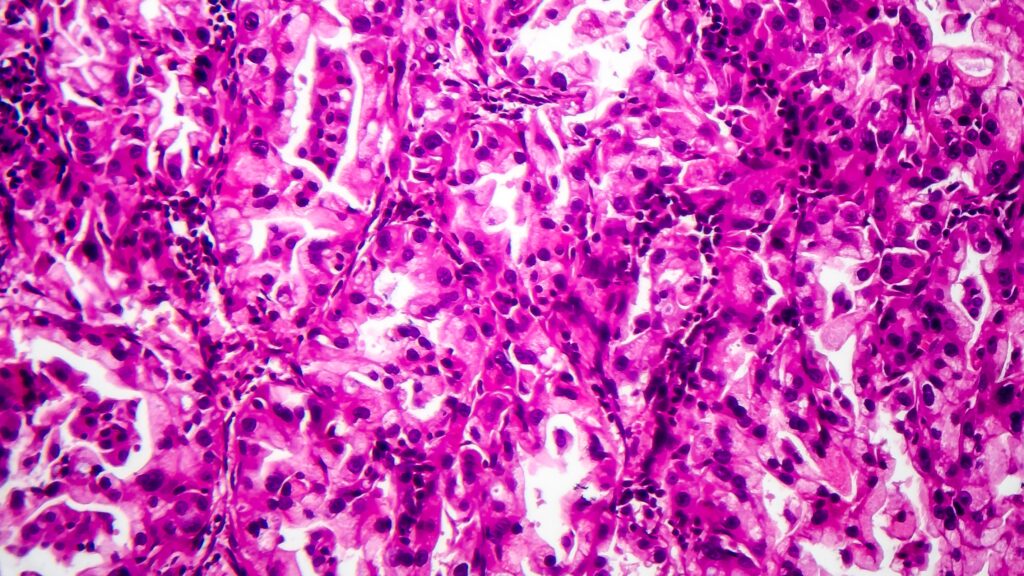

Summit Therapeutics hits doable snag on lung most cancers drug seen as blockbuster

Summit Therapeutics could have a geography drawback with its lung most cancers drug ivonescimab.